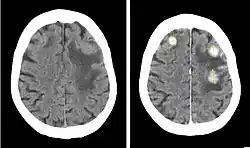

Iobitridol (trade name Xenetix) is a pharmaceutical drug used as an iodine-based radiocontrast agent in X-ray imaging.[1] It is injected into blood vessels, joints, or body cavities such as the uterus, and filtered out by the kidneys.[2] Its most common adverse effect is nausea. Severe allergic reactions are rare.[1][2]

Iobitridol is used for intravenous urography (imaging of the urinary system via a vein), angiography (imaging of blood vessels), angiocardiography (heart and coronary arteries), arthrography (joints), hysterosalpingography (uterus and fallopian tubes), and imaging of the cranium and the whole body.[2] It is approved for use in adults and children.[5]

Iobitridol is an iodine-containing radiocontrast agent.[2][5] The iodine atoms readily absorb X-rays, resulting in better contrast in radiography images.[9] The quality of images made with this drug is equally good as with other low– or medium–osmolarity iodinated contrast agents such as iopamidol or iohexol.[5]